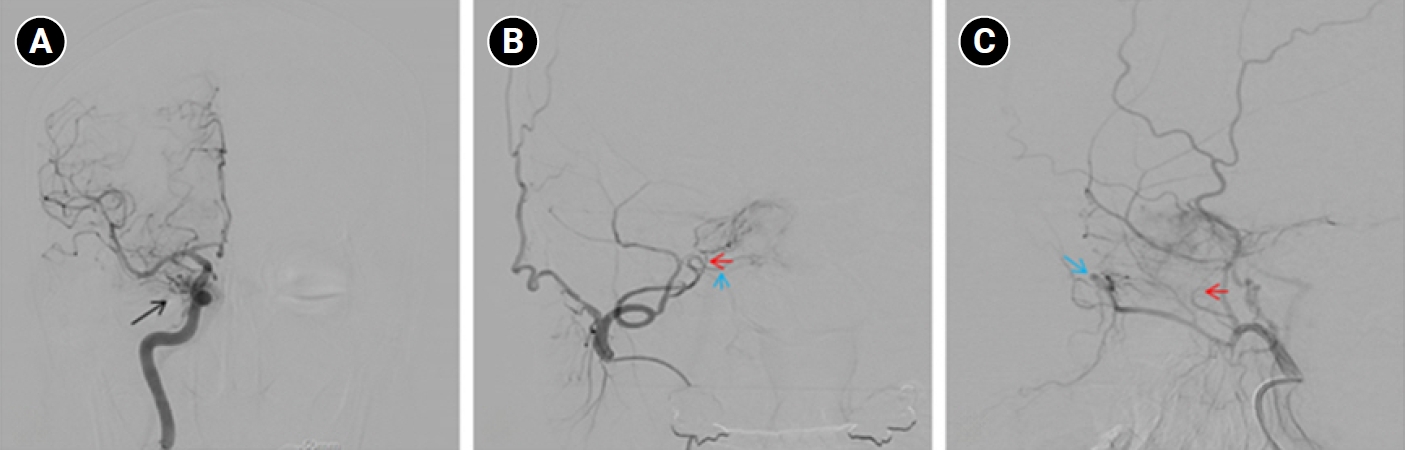

Baseline hematology and chemistry—including complete blood count, electrolytes, renal/hepatic indices—and coagulation tests (prothrombin time/international normalized ratio, activated partial thromboplastin time) were within reference limits. Erythrocyte sedimentation rate and C-reactive protein were normal. A focused screen for secondary trigeminal neuropathy (thyroid-stimulating hormone, vitamin B12, HbA1c) was negative. There were no clinical signs of infection. Brain magnetic resonance imaging (MRI) demonstrated high flow related signal in the right cavernous sinus and asymmetric dilation of the superior ophthalmic veins (right>left), raising suspicion for a CCF (Figure 1). Definitive diagnosis was established on digital subtraction angiography (DSA), which identified a right CCF. DSA demonstrated an indirect CCF supplied by the right meningohypophyseal trunk of the ICA and by right ECA branches, including the internal maxillary artery and the cavernous branch of the middle meningeal artery, consistent with Barrow type D (Figure 2).6 Barrow type D denotes an indirect, low-flow fistula with dual ICA/ECA dural supply; unlike direct type, indirect types present more insidiously, and symptom patterns are largely determined by venous drainage, with posterior drainage often manifesting as CN VI palsy and headache (Table 1).1,3,6,7 The fistula was treated with transvenous Onyx embolization. On post-procedure day 1, non-contrast time-of-flight magnetic resonance angiography (TOF-MRA) demonstrated a marked reduction of flow related hyperintensity within the right cavernous sinus, and the right superior ophthalmic vein caliber decreased from 6.63 to 4.61 mm (Figure 3A, B). Follow-up DSA (at 3 weeks) likewise showed substantial attenuation of fistulous opacification (Figure 3C), supporting a significant interval decrease in arteriovenous shunting. At 1–2 weeks, the patient reported an ~80%–90% reduction in dental/lower-facial pain and bifrontal headache from NRS 7–8 to 1–2. By 1 month, red-glass testing demonstrated resolution of primary-position diplopia. Formal prism measurements were unavailable; bedside ocular-motor grading was recorded using a standard duction underaction scale (–4 to 0). Right abduction improved from –1 to 0, and primary-position diplopia was absent at distance and near, consistent with recovery from abducens palsy.

Brain magnetic resonance imaging (MRI) findings. (A, B) Non-contrast time-of-flight magnetic resonance angiography shows a high flow-related signal (red arrows) within the right cavernous sinus. (C) Contrast-enhanced T1-weighted MRI demonstrates asymmetric dilation of the superior ophthalmic veins (blue arrow), more prominent on the right.